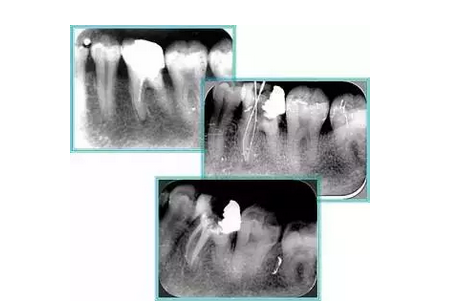

7. 器械折斷

右圖及下圖為器械折斷的 X 線片。箭頭處示折斷器械。

解決方法: ( 1 )取出。 ( 2 )通過。 ( 3 )重新確定工作長度,充填。 ( 4 )根尖手術(shù)。

器械折斷可以不用取出,取出的原因多是患者心理因素。留在里面的器械關(guān)鍵是進(jìn)行消毒,預(yù)防性使用抗感染藥物,預(yù)防感染。